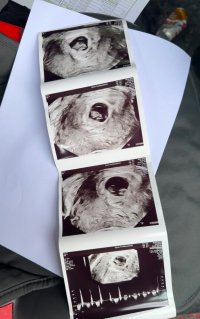

Innvendig. Best å se så tidlig med innvendig ulSå godt å se <3 Er det utvendig ultralyd?![]()

Lille vennEt lite blinkende hjerte med god hjertelydEr i uke 7, så mellom 7+4 og 7+5 er riktig enda. Hun målte lille til 1 cm, men hun gjorde det så fort, så ikke sikkert det stemmer.

Vis vedlegget 454915